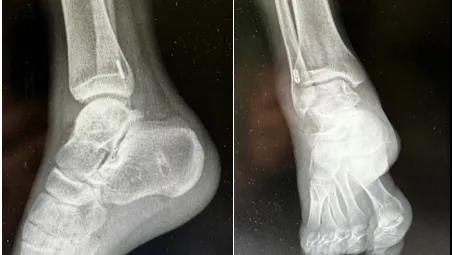

术后影像学显示踝关节恢复稳定,隧道位置良好